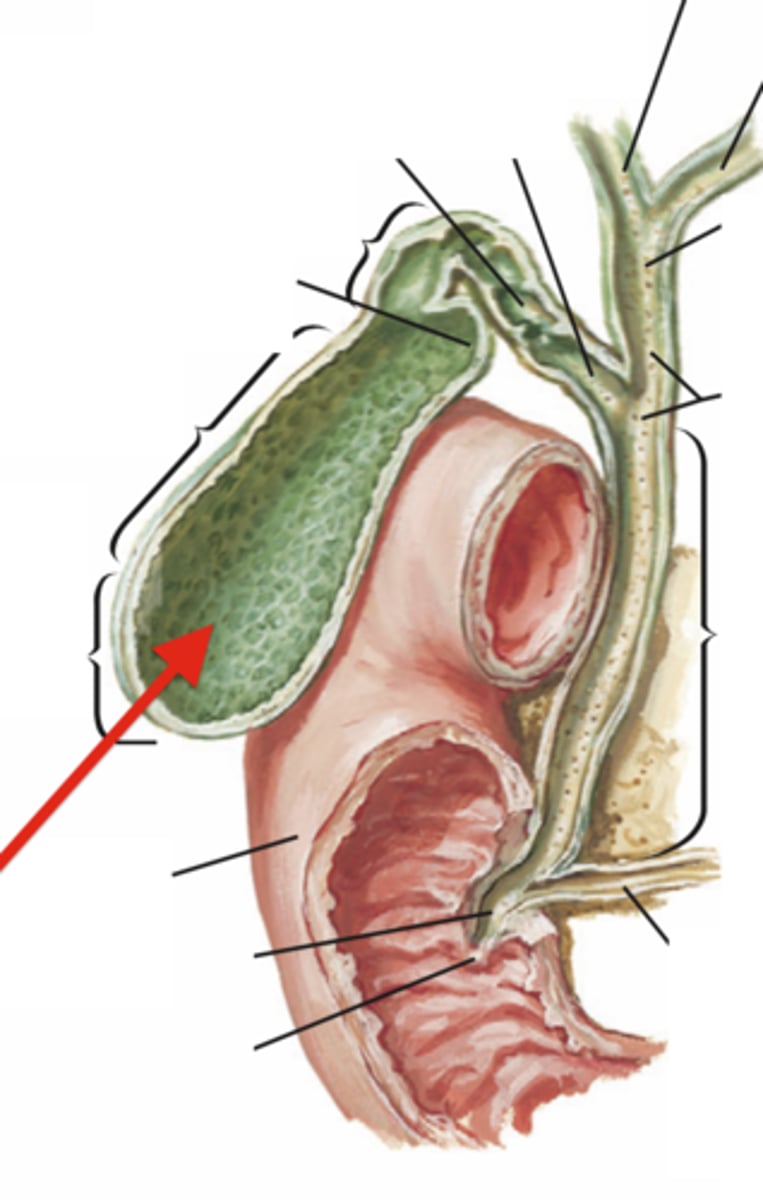

portal triad

what is in this structure

common bile duct

common hepatic duct

cystic duct

hepatic portal vein

gallbladder

fundus (gallbladder)

body (gallbladder)

neck (gallbladder)